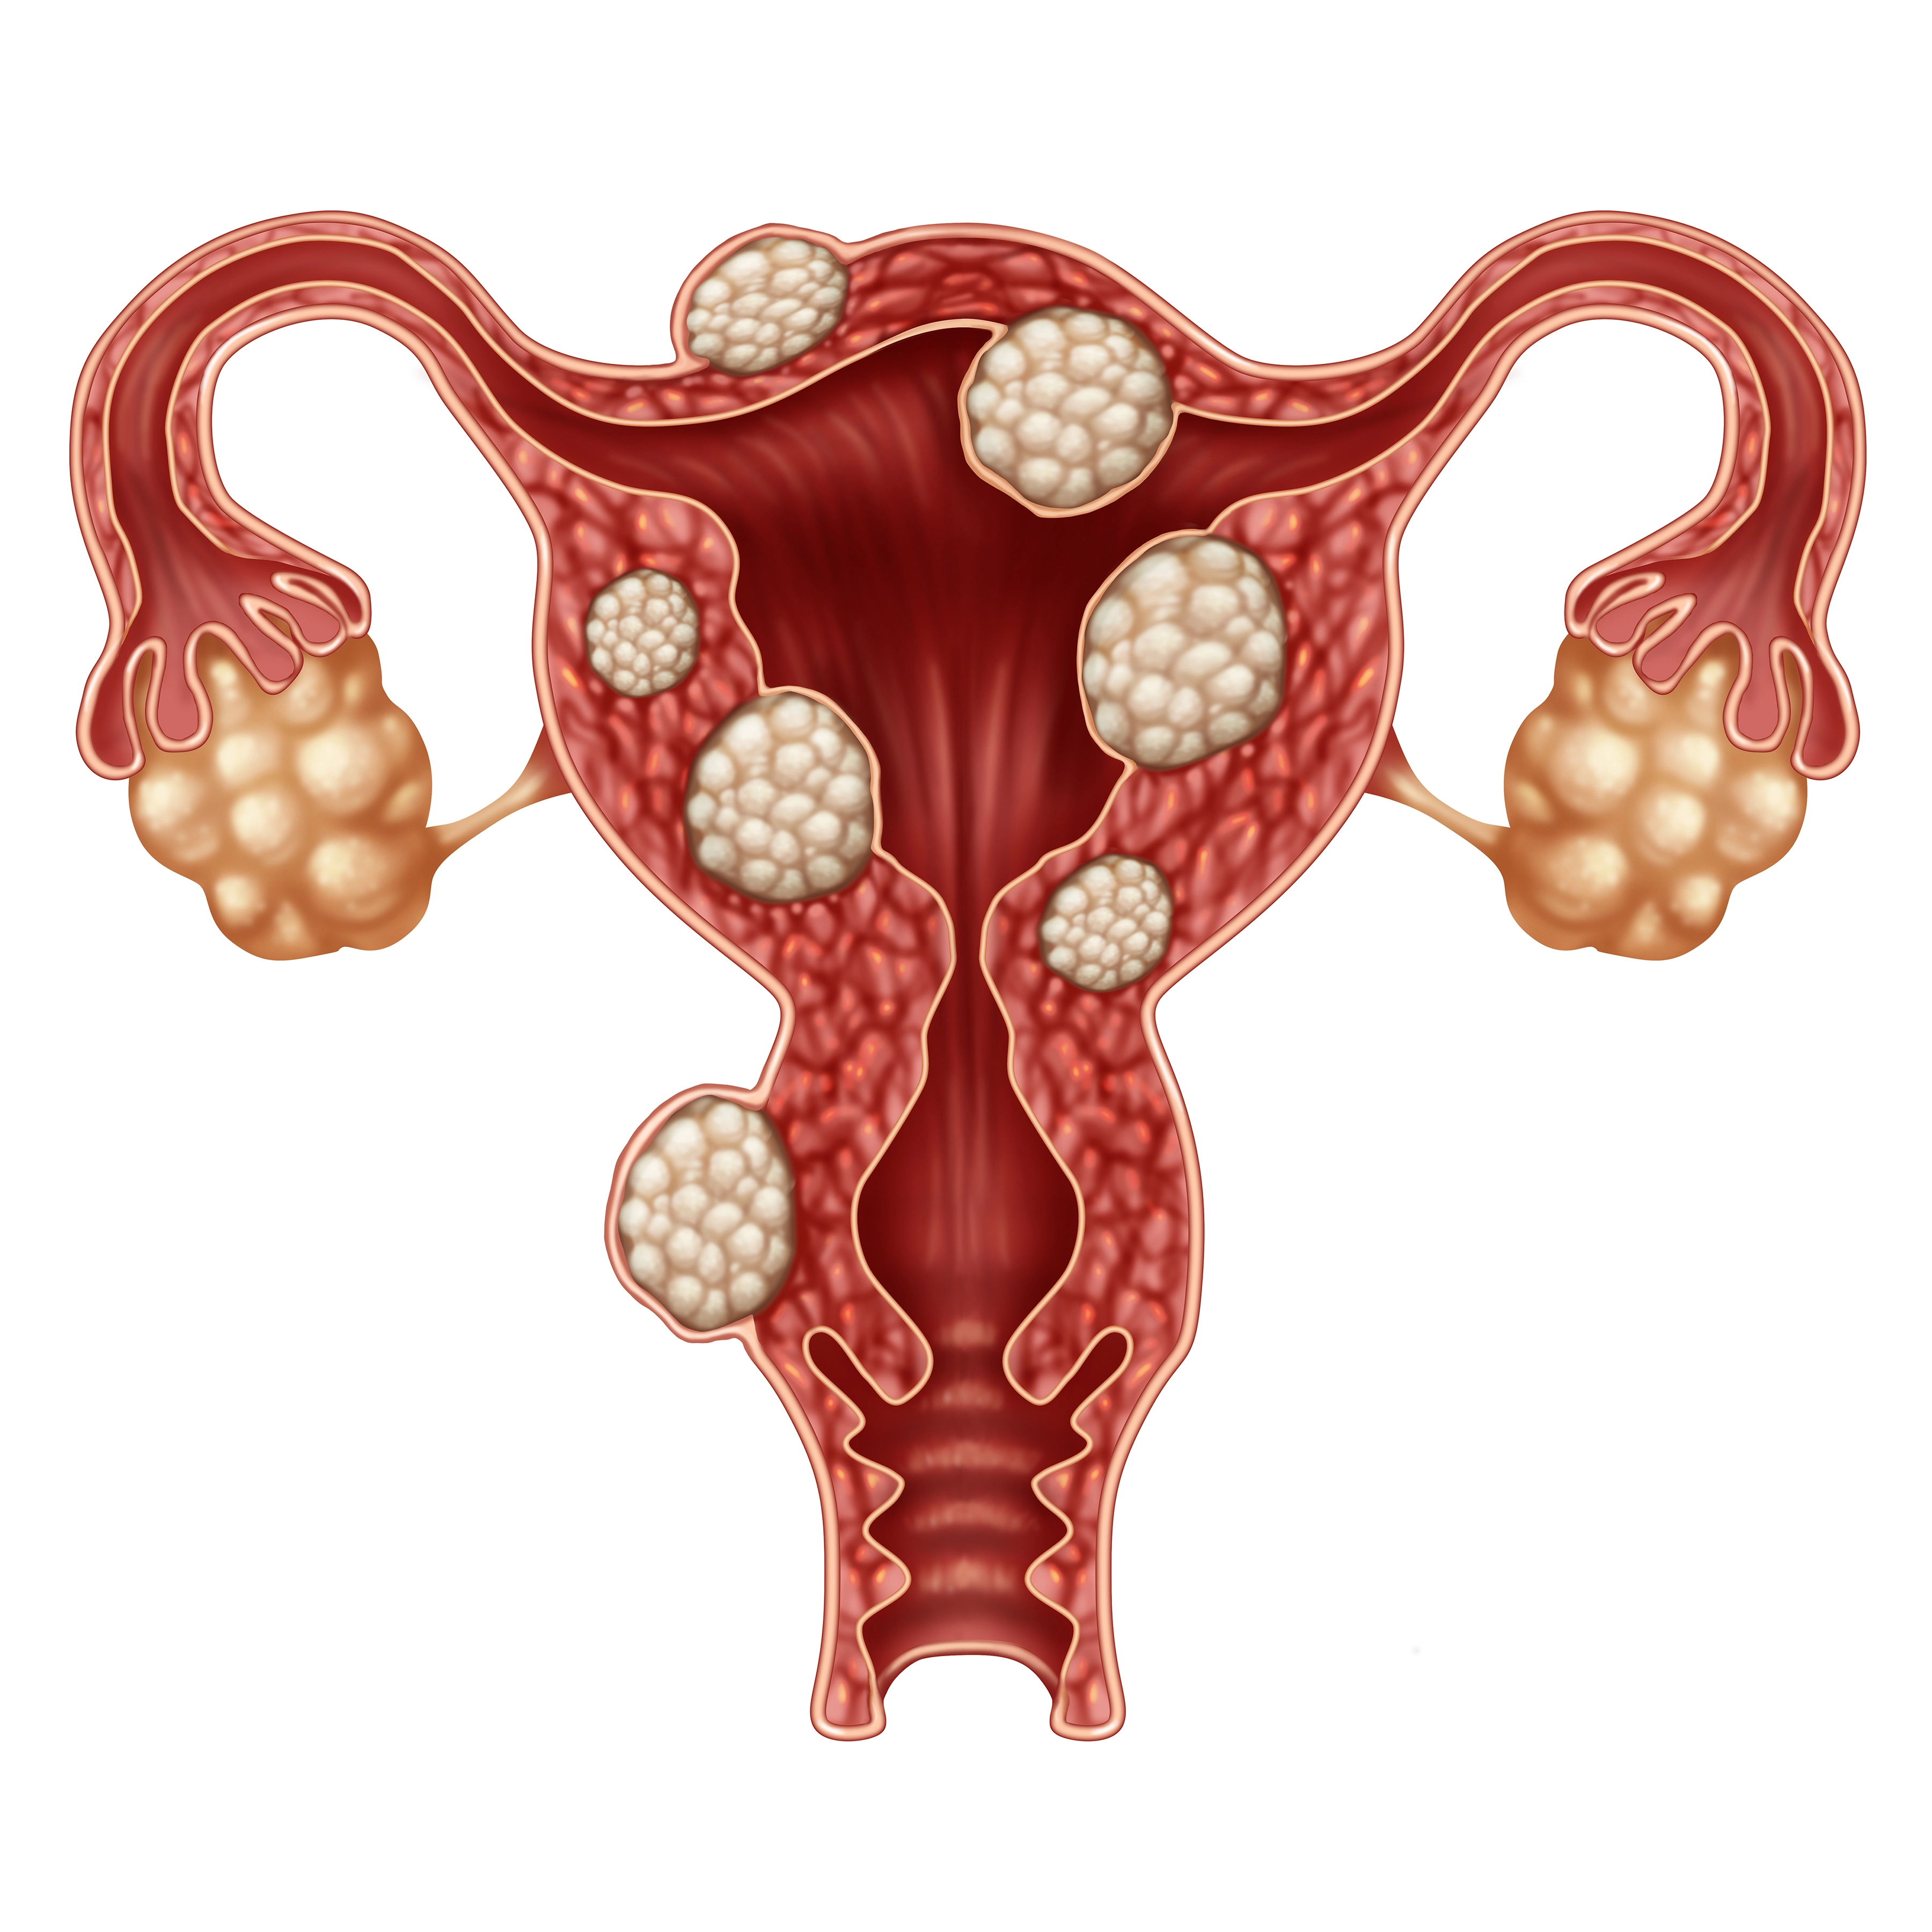

Fibroid Embolization

After completing my medical training, residency and advanced fellowship in Vascular & Interventional Radiology from the best institutes in the country, I’ve dedicated my career to offering precise, minimally invasive treatments for wide variety of complex conditions like uterine fibroids, thyroid nodules, varicose veins, prostate enlargement, knee joint pains, liver diseases, cancer and many more. Although technology enables precision in Interventional Radiology, but it is compassion, empathy, and ethics that bring meaning to medicine and guide every decision I make in my patient treatment.